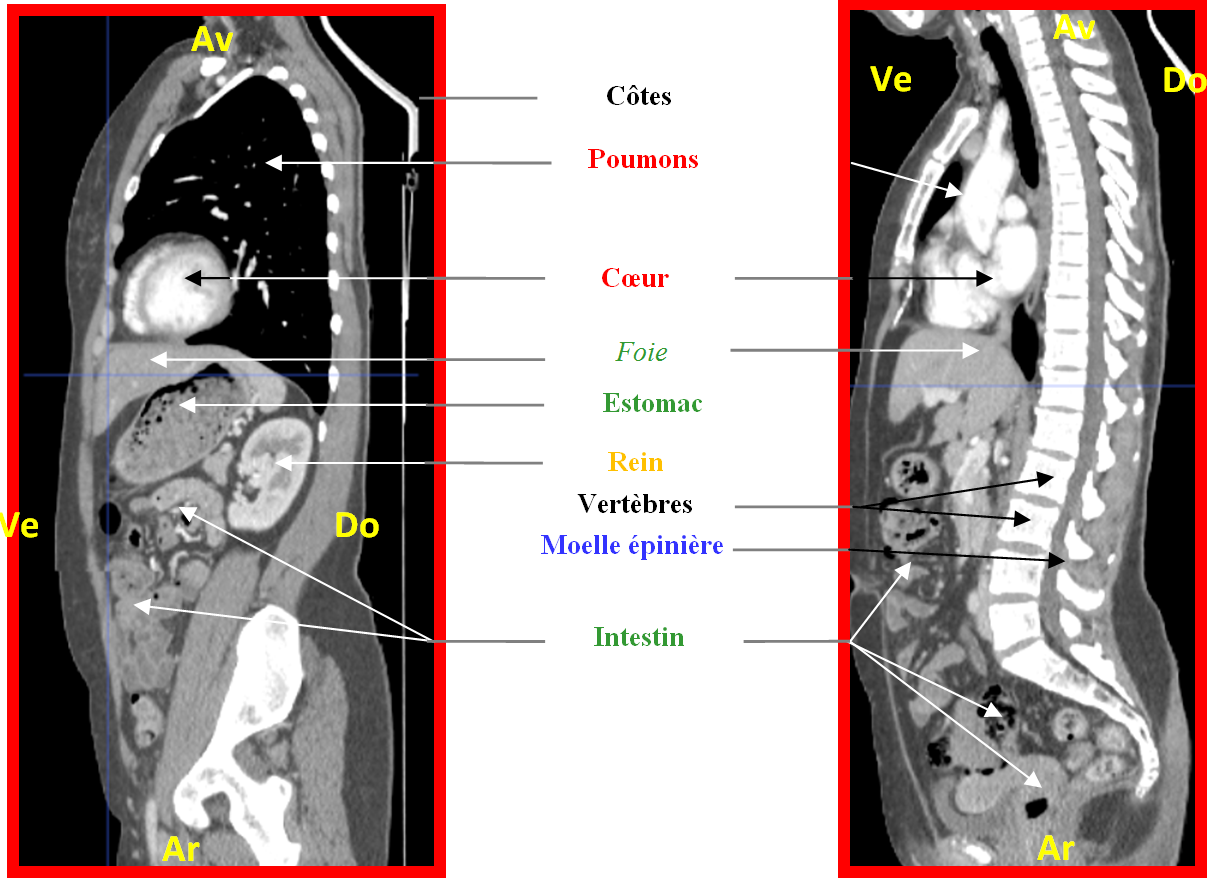

Homme sagittal